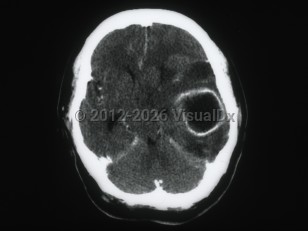

Brain abscessBrain abscess